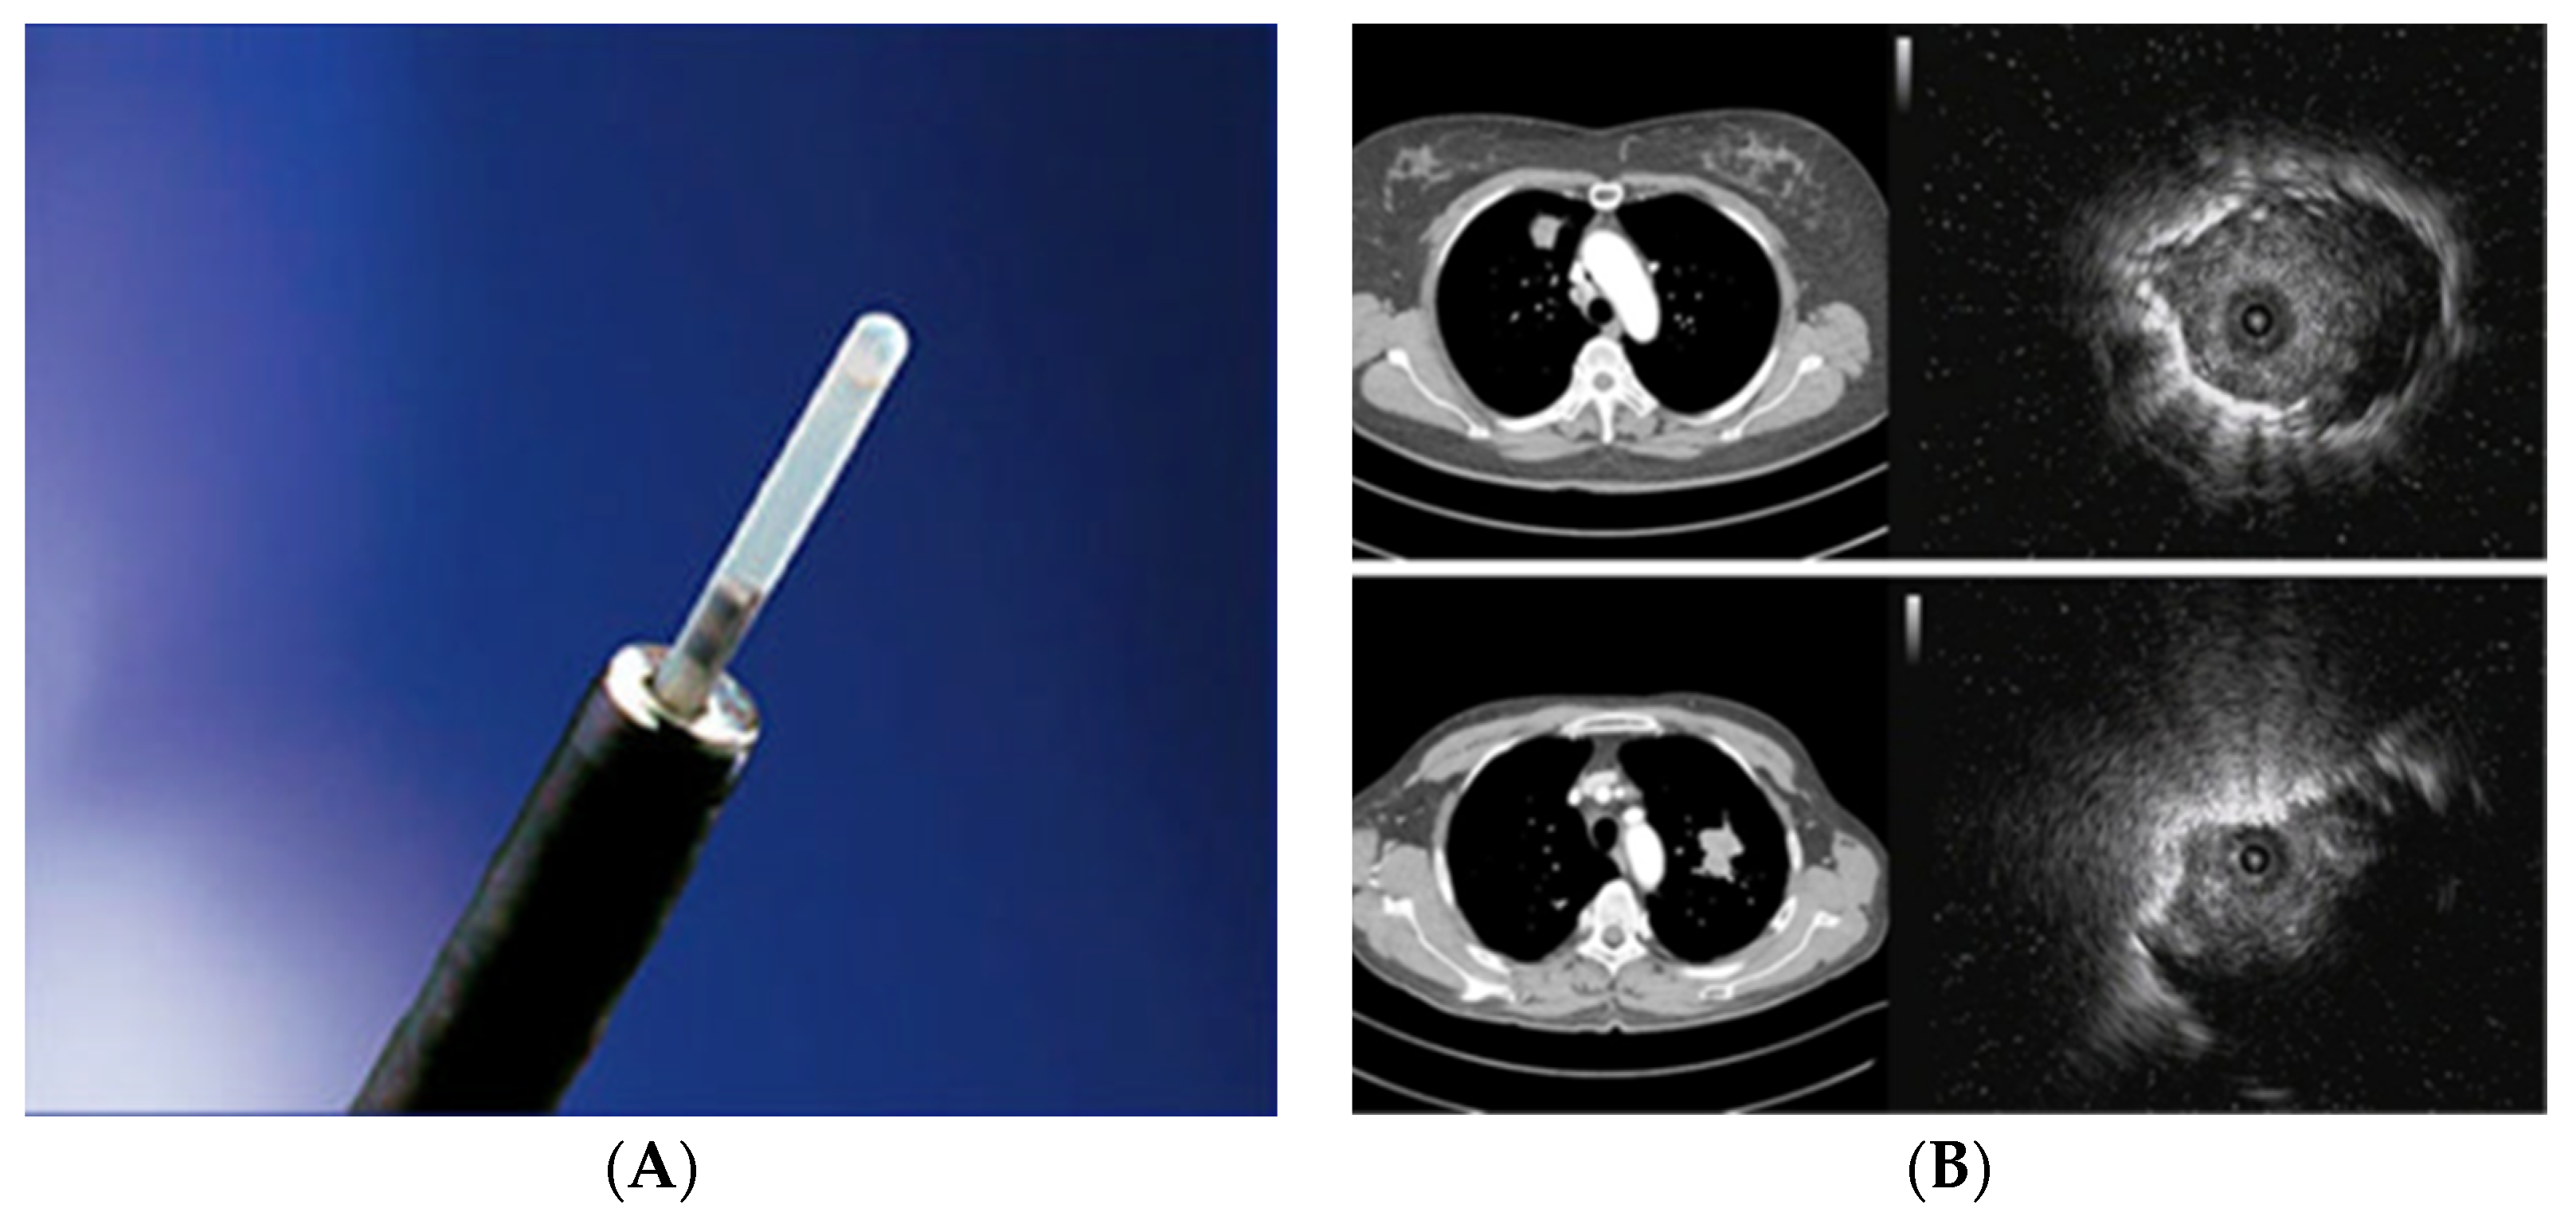

2.2. Radial Probe—Endobronchial Ultrasound with a Guide Sheath in the Diagnosis of Peripheral Lung Lesions

- Kurimoto, N.; Murayama, M.; Yoshioka, S.; Nishisaka, T. Analysis of the internal structure of peripheral pulmonary lesions using endobronchial ultrasonography. Chest 2002, 122, 1887–1894. [Google Scholar] [CrossRef]

- Kikuchi, E.; Yamazaki, K.; Sukoh, N.; Kikuchi, J.; Asahina, H.; Imura, M.; Onodera, Y.; Kurimoto, N.; Kinoshita, I.; Nishimura, M. Endobronchial ultrasonography with guide-sheath for peripheral pulmonary lesions. Eur. Respir. J. 2004, 24, 533–537. [Google Scholar] [CrossRef]

- Moon, S.M.; Choe, J.; Jeong, B.H.; Um, S.W.; Kim, H.; Jung Kwon, O.; Lee, K. Diagnostic performance of radial probe endobronchial ultrasound without a guide-sheath and the feasibility of molecular analysis. Tuberc. Respir. Dis. 2019, 82, 319–327. [Google Scholar] [CrossRef] [PubMed]

- Kim, I.; Eom, J.S.; Kim, A.R.; Lee, C.H.; Lee, G.; Jo, E.J.; Kim, M.H.; Mok, J.H.; Lee, K.; Kim, K.U.; et al. Molecular analysis of small tissue samples obtained via transbronchial lung biopsy using radial probe endobronchial ultrasound. PLoS ONE 2019, 14, e0212672. [Google Scholar] [CrossRef] [PubMed]

- Guisier, F.; Salaün, M.; Lachkar, S.; Lamy, A.; Piton, N.; Obstoy, B.; Sabourin, J.-C.; Thiberville, L. Molecular analysis of peripheral non-squamous non-small cell lung cancer sampled by radial EBUS. Respirology 2016, 21, 718–726. [Google Scholar] [CrossRef] [PubMed]